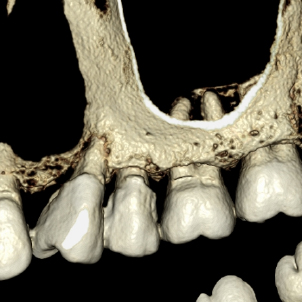

La RDD es muy exacta y fácil de interpretar como las placas convencionales de Rayos X; pero además puede ser aumentada 300 veces su tamaño, puede modificarse el contraste y ajustarse el tono del color y así detectar los problemas escondidos a las placas convencionales.